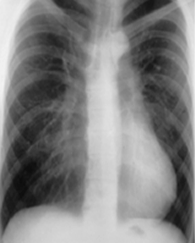

En la Rx PA hay desplazamiento del corazón, con disminución de la densidad del ángulo cardiofrénico derecho. Con la proyección lateral, se identifica el grado de depresión esternal. (4). (Fig 17).

Fig 17. Pectum excavatum.

Rx PA. Desplazamiento de la silueta cardiaca hacia la izquierda, lo que hace sospechar pectum excavatum.